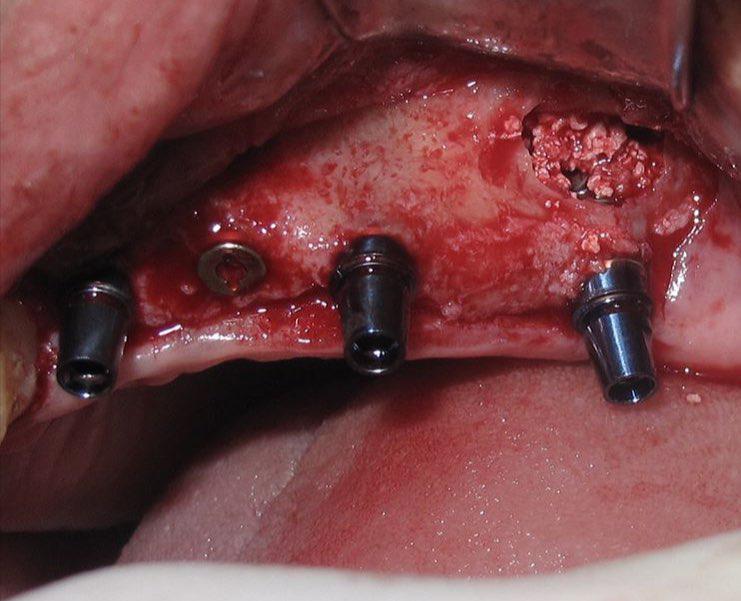

جراحی گذاشتن ایمپلنت های دندانی جهت جایگزینی دندانهای از دست رفته

جراحی پیوند استخوان جهت افزایش میزان استخوان و آماده سازی برای گذاشتن ایمپنت

جراحی سینوس لیفت بصورت باز و بسته برای گذاشتن ایمپلنت